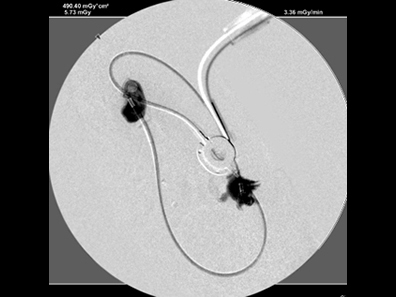

造影で漏れがないか何度も確認

必ず透視下にて漏れがないか何度も確認をします。 透視をしないとシステムや装着部分からの漏れが確認されたり、トラブルが考えられます。

実際、他院で装着して漏れがあるなどの相談をうけることがしばしばあります。

透視下にて実施すれば適切な位置に装着できます。

綺麗につければ感染や漏れもほとんどなく、経過はとても良好です。